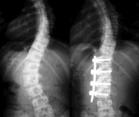

特发性脊柱侧凸

青春期特发性脊柱侧凸是最常见的侧凸,女性多于男性,以胸弯右侧凸为多。对青春期侧凸治疗最重要的是按Risser征评价患者发育时期。对20°以下发育成熟的患者,可不予以治疗。若对未成熟患者,可行体疗,每半年拍片随诊观察直至发育成熟。如侧凸超过25°,生长发育尚未成熟,应尽早给以Milwaukee支具或胸腰骶支具治疗,并配合以体疗或电刺激治疗,直到整个脊柱生长停止和risser征4级(Ⅳ度)以上,才去掉支具。对仍有生长发育的青春期侧凸Cobb角在40°以上者,不应再保守治疗,而应直接行脊柱矫形固定融合术,一般以Harrington器械为最常用。